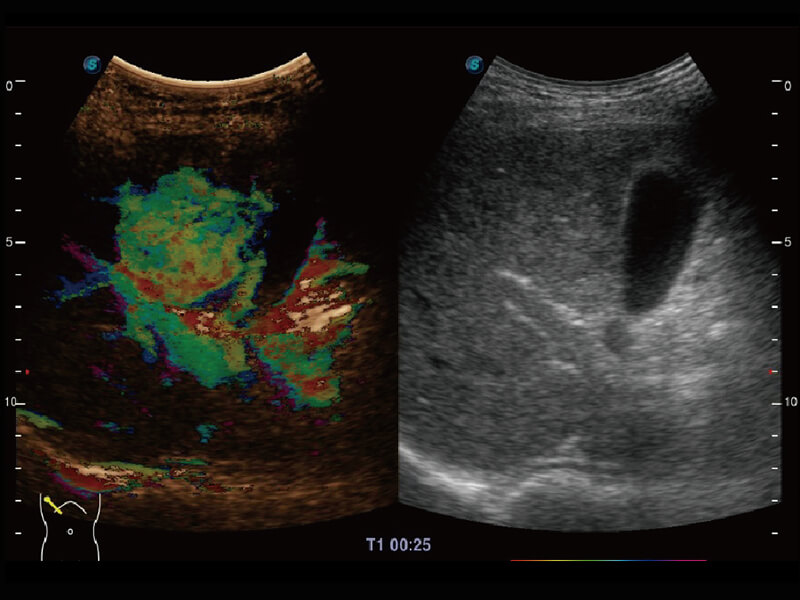

彩色多普勒超声诊断系统

S60探头工艺,从前端信号处理每一个环节采集无损声学数据,真实还原组织原貌,再现解剖细节。

超宽频带技术,为容积成像带来优质的二维图像基础,为您呈现丰富的结构细节,栩栩如生地展示宝宝的宫内形态以及各种组织的立体结构。